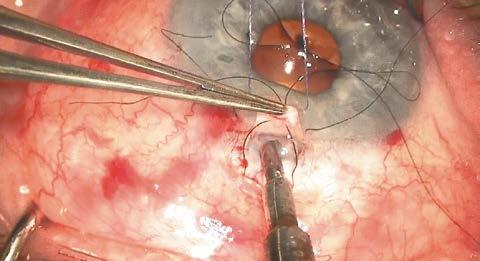

Ante este escenario, donde la dureza nuclear y la estrechez del espacio de maniobra hacían de la facoemulsificación una opción de alto riesgo para el endotelio, se optó por una MSICS con abordaje temporal para minimizar el riesgo endotelial y proteger la ampolla filtrante superior. Se confeccionó un túnel escleral de 7 mm para una extracción del núcleo sin estrés mecánico (Figura 5). Se implantó una lente intraocular de tres piezas bajo viscoelástico y se aseguró la hermeticidad con un único punto corneoescleral (Figura 6).

Figura 5. Túnel escleral de la MSICS

Figura 6. Sutura del túnel escleral con un punto de nylon